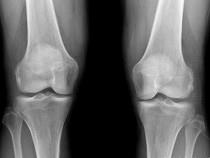

问题 女,65岁,右膝痛,活动受限,请结合图像,选出最可能的诊断 ( )

选项 A、类风湿关节炎 B、痛风 C、创伤性关节炎 D、退行性骨关节病 E、神经性关节病

答案 D